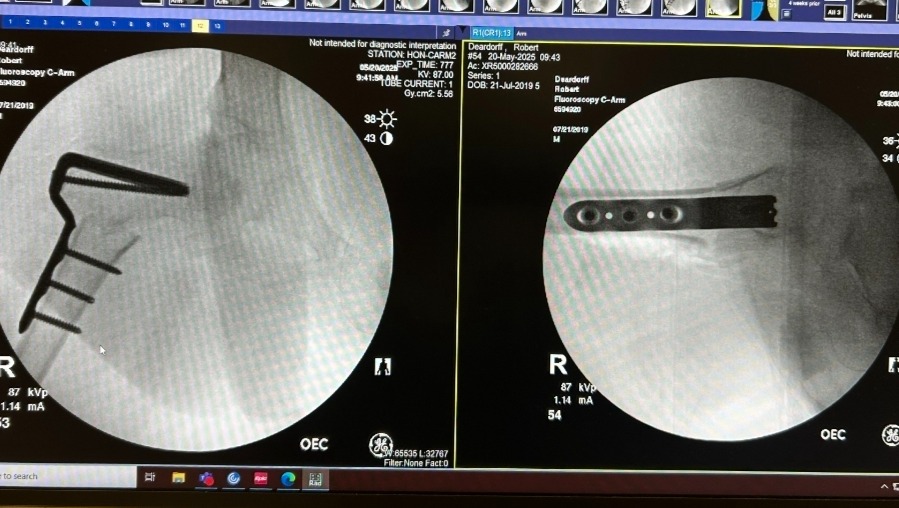

Robbie then underwent a much more invasive procedure called a femoral varus de-rotational osteotomy. During this surgery, doctors cut and reshaped his femur to better position the femoral head inside the hip socket. The bone was stabilized using metal plates and screws.

X-ray taken May 20, 2025, following his femoral osteotomy